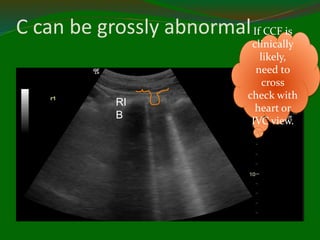

C = Pleural line abnormalities

Acute

inflammation

Old fibrosis.

Indicates

abnormal

interstitium

C can be grossly abnormalIf CCF is

clinically

likely,

need to

cross

check with

heart or

IVC view.

RI